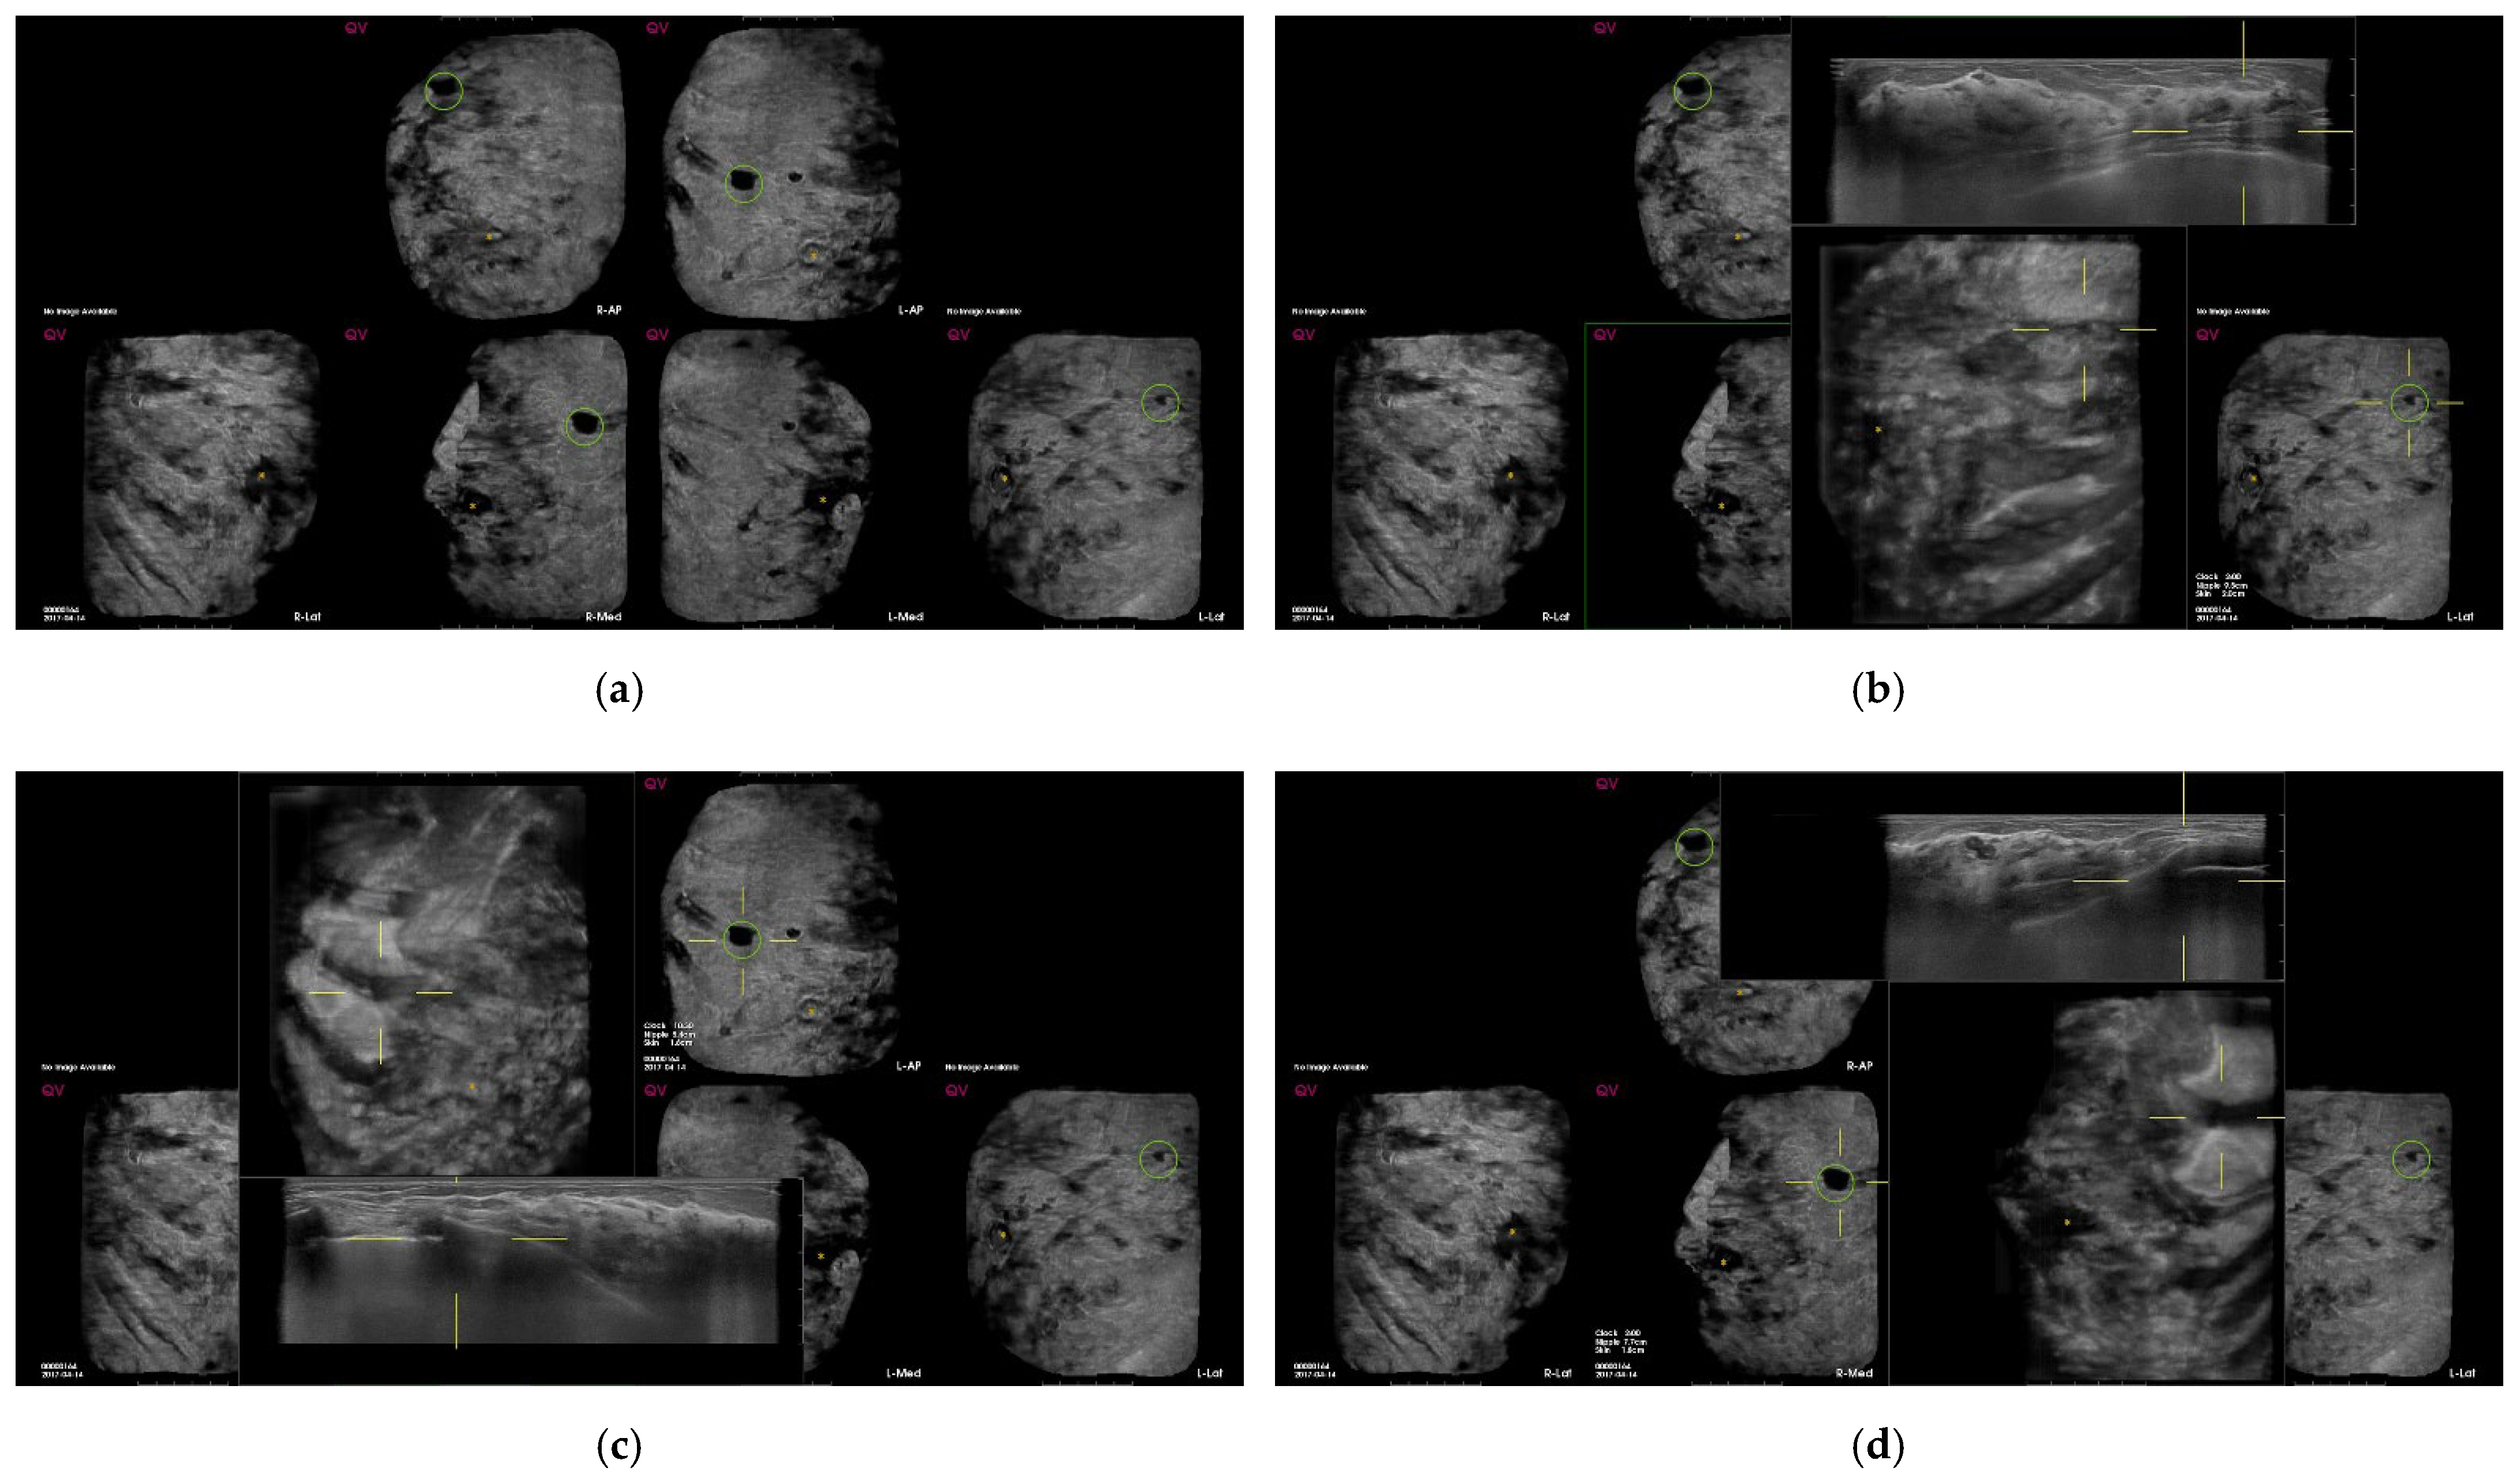

| False-positive marks for pseudolesions | 459 | 86 |

| Marginal shadowing | 209 | 39.1 |

| Cooper’s ligament shadowing | 143 | 26.8 |

| Periareolar shadowing | 64 | 12 |

| Rib | 37 | 6.9 |

| Skin lesion | 6 | 1.1 |